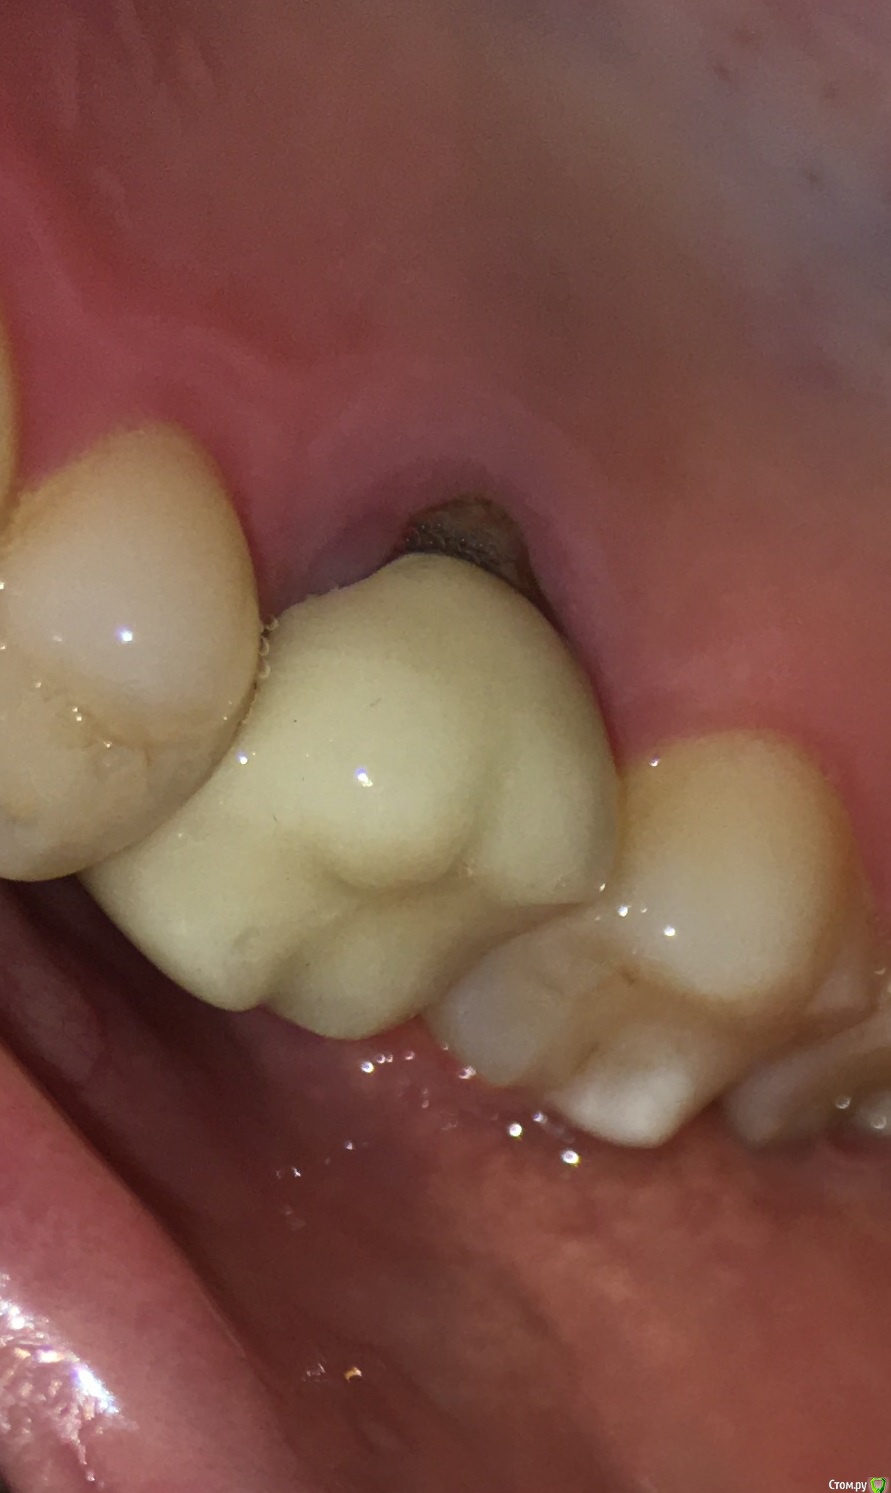

MichaelV Опубликовано 9 октября, 2019 Поделиться Опубликовано 9 октября, 2019 (изменено) Прошу подсказать специалистов.Несколько месяцев назад на 16-ый зуб поставили вкладку (однокоренную) и сделали коронку. Коронка стояла на временном цементе, сейчас отвалилась и надо идти ставить на постоянку. Решил внимательно рассмотреть, как она стоит. С внешней стороны особых вопросов нет - по десне идет тонка темная полоска на стыке коронки и вкладки. С внутренней стороны есть заметная щель. Посмотрите, пожалуйста, фото - нормально ли это или все-таки так быть не должно?Спасибо!(доп. информация - мне 36, нерв был удален лет 15-20 назад, 2 года назад перепломбировал каналы, но вкладку поставил только в этом году. Рад буду услышать рекомендации и советы по продлению жизни зуба в свете текущей ситуации). Изменено 9 октября, 2019 пользователем MichaelV Ссылка на комментарий

chervoncevdaniil Опубликовано 9 октября, 2019 Поделиться Опубликовано 9 октября, 2019 Честно говоря довольно странное решение для одиночной коронки в боковом отделе,это инициатива доктора или ваша была?По теме,может конечно вы ее не до конца одели или временный цемент немного завышает,а на постоянном будет все ОК,но судя по этому фото не совсем точно прилегает коронка Ссылка на комментарий

MichaelV Опубликовано 9 октября, 2019 Автор Поделиться Опубликовано 9 октября, 2019 Скорей всего моя (Семь раз отмерь - один раз отрежь), я всегда настороженно и внимательно отношусь к необратимым вещам, и если можно лишний раз проверить и подстраховаться - лучше так и сделать. Или я в этом случае заблуждаюсь? Тут второй вопрос у меня - насколько реально такую коронку, установленную на постоянный цемент, потом снять и заменить на другую?С внешней сотроны зазор минимальный, как раз м.б. на завышение временного цемента. Такой зазор с внутренней стороны - это очевидный брак, требующей переделки? Ссылка на комментарий